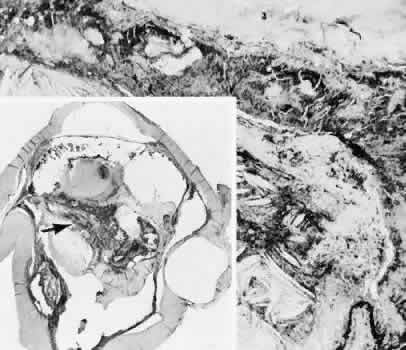

Epithelial downgrowth (ingrowth) (Fig. 44) is one of the most serious causes of pseudophakic glaucoma, in which surface epithelium (probably from the conjunctiva) grows into the anterior chamber. This condition is more likely to occur with fornix-based conjunctival flaps than with limbus-based flaps and in eyes with problems in wound closure, such as vitreous loss, wound incarceration of tissue, delayed reformation of the anterior chamber, or frank rupture of the limbal incision, and when instruments such as iridectomy forceps are contaminated with surface epithelium before they are introduced into the eye. Epithelial downgrowth causes an anterior chamber angle closure by means of peripheral anterior synechiae or lines an open anterior chamber angle and obstructs aqueous outflow mechanically. Histologically, the epithelium is seen to grow most luxuriously and in multiple layers on the iris where there is a good blood supply, but it tends to grow sparsely and in a single layer on the posterior surface of the avascular cornea. The epithelium may extend behind the iris, over the ciliary body, and even far into the interior of the eye.

Fig. 44. A case of epithelial downgrowth. A. The clinical findings are subtle and consist of a translucentmembrane on the posterior corneal surface, often contiguous with an ocular wound, characterized by a well-defined, linear leading edge. In this case, the leading edge is just above the corneal light reflex. B. In contrast, in this case, the leading edge is just below the corneal light reflex. The surgical procedure in both cases appears to have been complicated because of the presence of sector iridectomies. C. In this case, surface stratified squamous epithelium lines the posterior cornea (including the posterior aspect of the clear corneal wound) and extends over delicate trabecular tissue onto the anterior surface of the iris. The epithelium will adapt the tissue over which it grows to produce an adhesive surface appropriate to its attachment requirements. This adaptive process that is an advantage for the epithelium will permanently destroy the function of the trabecular meshwork over which the surface epithelium extends. D. The actual site of the fistula allowing the epithelium to gain access to the internal surfaces of the eye is rarely found on histologic sections. Higher magnification of the area of the wound, however, does show the presence of foreign material in the incision. Polarized material (inset) consistent with degenerating silk suture is present. Invasion of the epithelium along a suture tract is one possible route of entrance. (Hematoxylin-eosin stain with and without polarization; A, × 21; B, × 101)